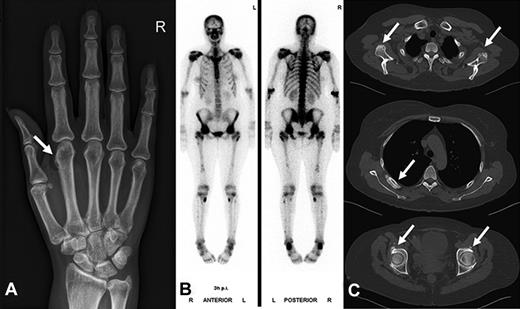

Serum fluoride levels. The boxplots represent median, IQR, and the whiskers, 95% confidence intervals. Serum fluoride levels were significantly elevated in patients receiving voriconazole (median, 157 μg/L; IQR, 97 μg/L) compared with itraconazole (median < 30 μg/L; IQR, 28 μg/L), posaconazole (median < 30 μg/L, IQR, 0 μg/L), and the control group without antifungal medication (median < 30 μg/L; IQR, 28 μg/L). P < .001 for all comparisons.

The main patient characteristics of overall 32 patients with hematologic malignancies taking voriconazole (n = 20), posaconazole (n = 8), and itraconazole (n = 4), as well as a hematologic patient control group (n = 11) not receiving antifungal therapy are shown in Table 2 and in more detail in Supplemental Tables 1 and 2 (available on the Blood Web site; see the Supplemental Materials link at the top of the online article). The 3 patients with proven voriconazole-induced skeletal disease were not included in this analysis. Serum fluoride levels were significantly elevated in patients receiving voriconazole (median, 157 μg/L; IQR, 97 μg/L) compared with itraconazole (median, < 30 μg/L; IQR, 28 μg/L), posaconazole (median, < 30 μg/L; IQR, 0 μg/L), and the control group without antifungal medication (median, < 30 μg/L; IQR, 28 μg/L; P < .001 for all comparisons; Figure 3). The fluoride level in the voriconazole treatment group was inversely correlated to the glomerular filtration rate (Spearman rank correlation coefficient = 0.74; P < .001; Figure 4). Radiologically typical skeletal disease (periosteal appositions, abnormal calcifications) was seen in the CT scan of 1 asymptomatic patient (5%) in the voriconazole group and none in the other treatment groups. Disseminated bone pain consistent with skeletal disease was present in 3 (15%) patients in the voriconazole group and none in the other treatment groups. No signs of skeletal disease were detected in 2 of these patients by chest CT scan, whereas the third patient had no radiologic examinations performed during the observation phase. Additional fluorinated drugs were given in only 1 patient (posaconazole group), and no increase in serum fluoride level was noted.